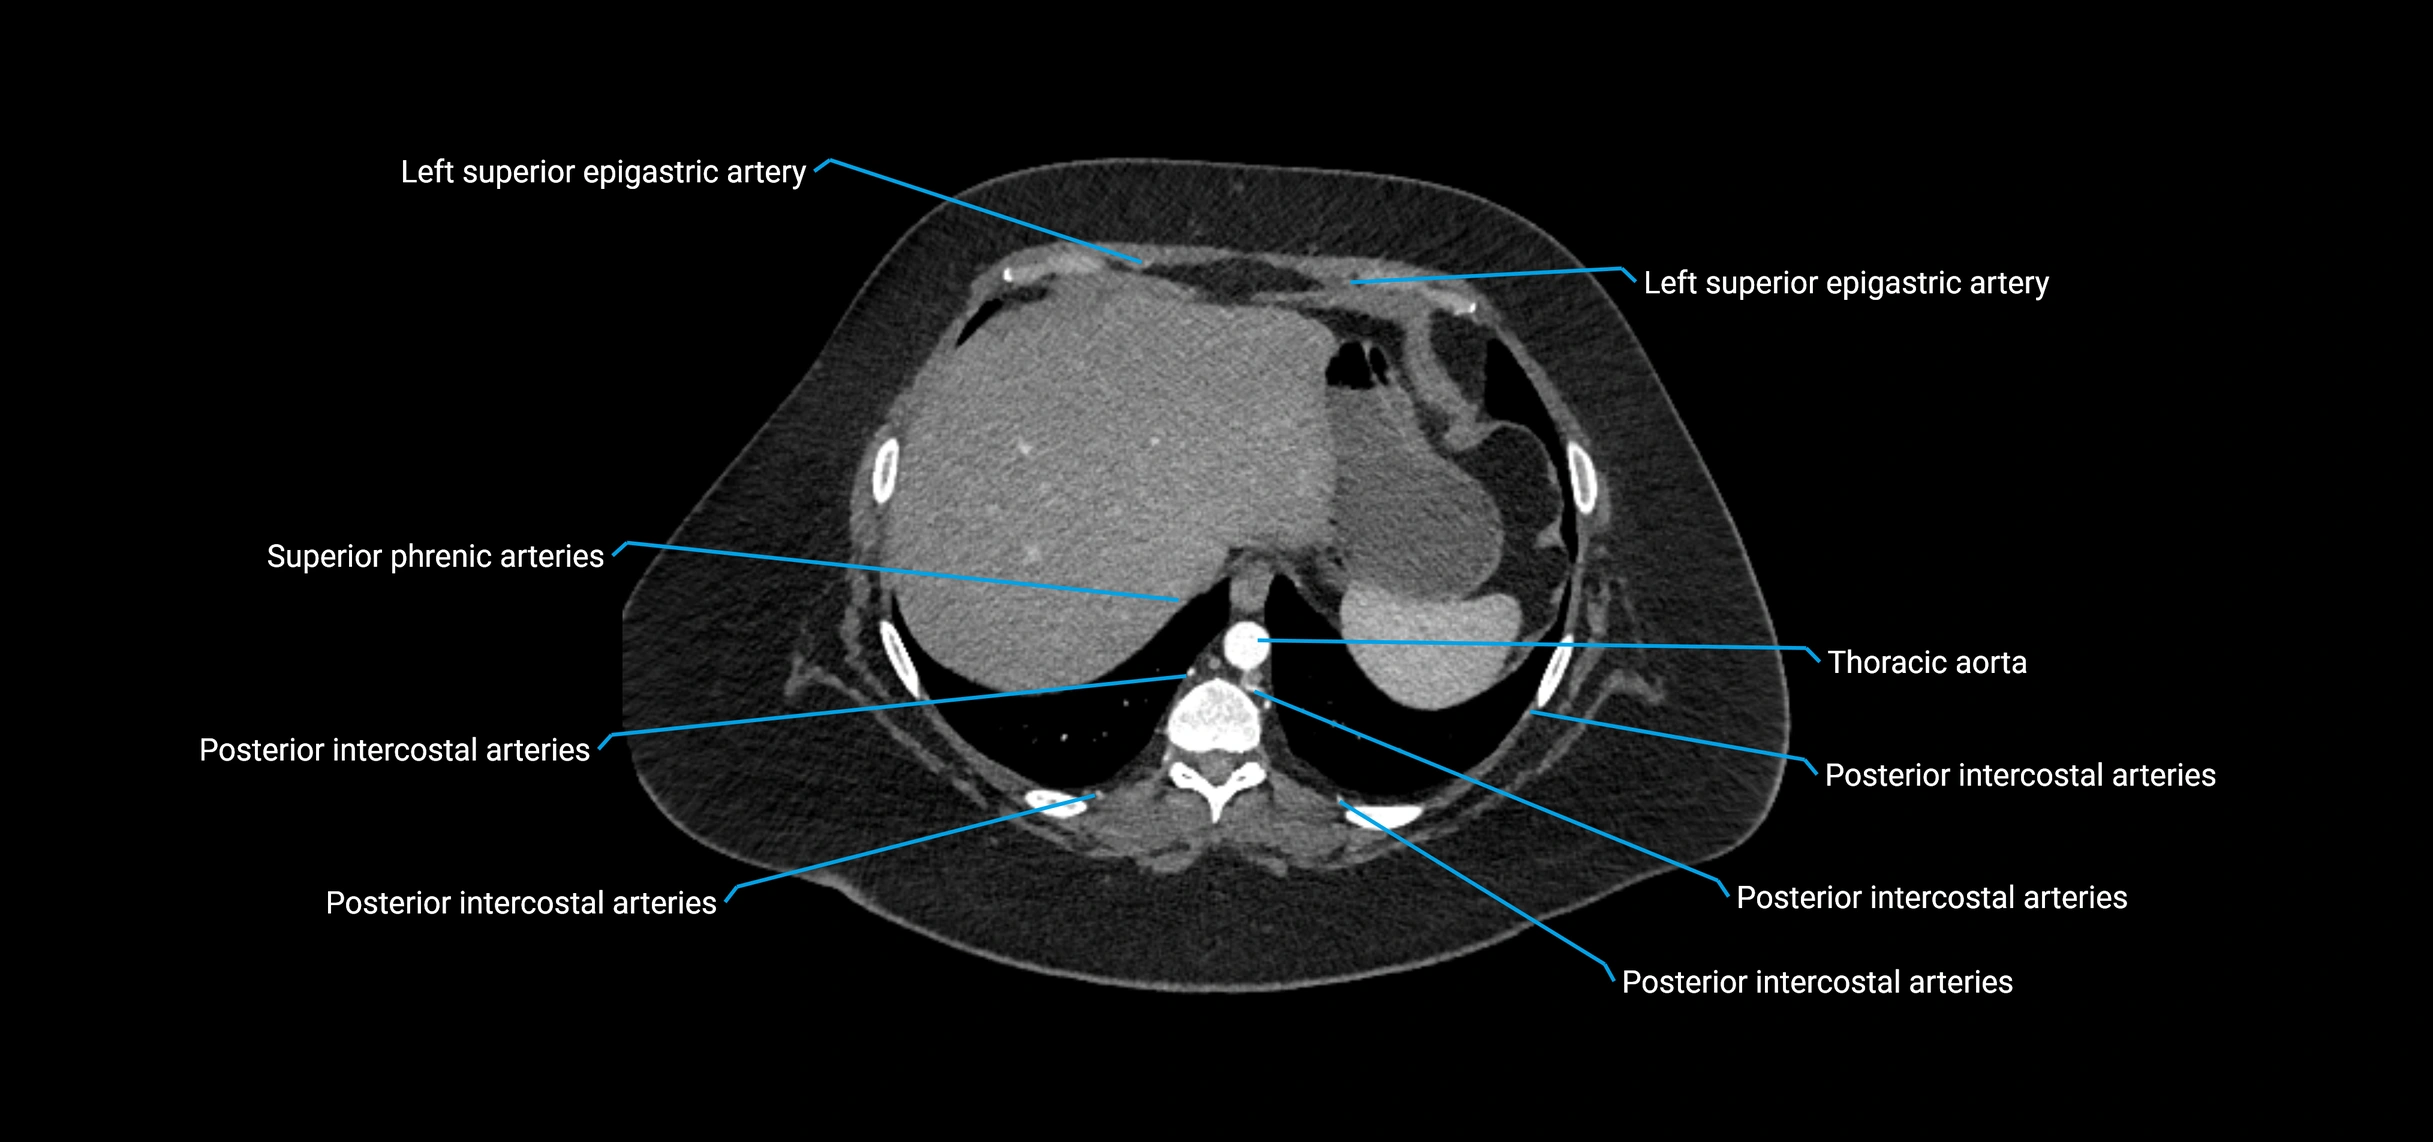

MRI Appearance

T1-weighted images:

• Flowing blood appears as a signal void (black lumen)

• Vessel wall appears as a thin hypointense rim; retroperitoneal fat enhances contrast

T2-weighted images:

• Lumen remains a signal void due to flow

• Adjacent edema, hematoma, or aneurysm wall thrombus may appear hyperintense